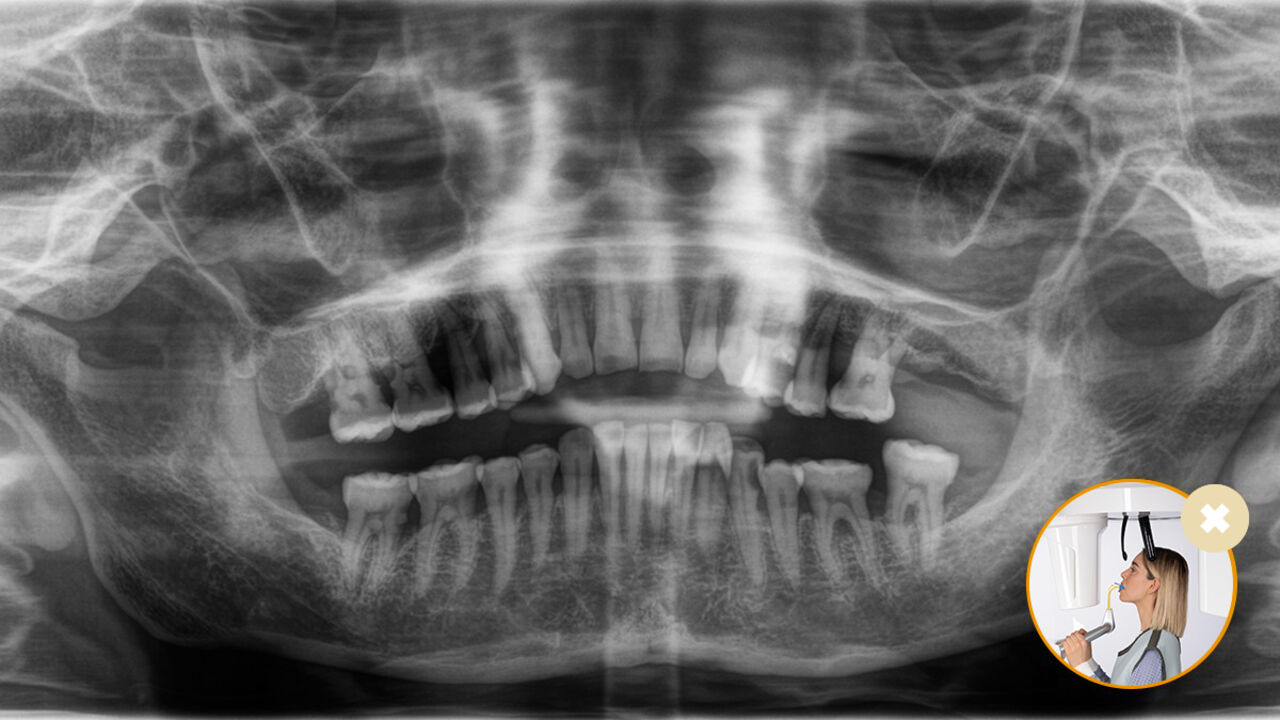

Relaxed and pleasant procedures are equally important for everyone, the patients and the staff alike. It is satisfying and motivating when everything goes according to plan and things go smoothly. The use of Orthophos or Axeos with Sidexis 4 provides you with targeted support. The X-ray systems are simple to use, yet unique in their diagnosis possibilities.. This ensures that every aspect of the treatment process creates a positive experience.

Correct patient positioning leads to high image quality to support an accurate diagnosis and facilitates and improves patient experience.

This is our 10-point concept for easy patient positioning and X-ray imaging. It is primarily about two things: high image quality and comfort for the patient and the assistant.